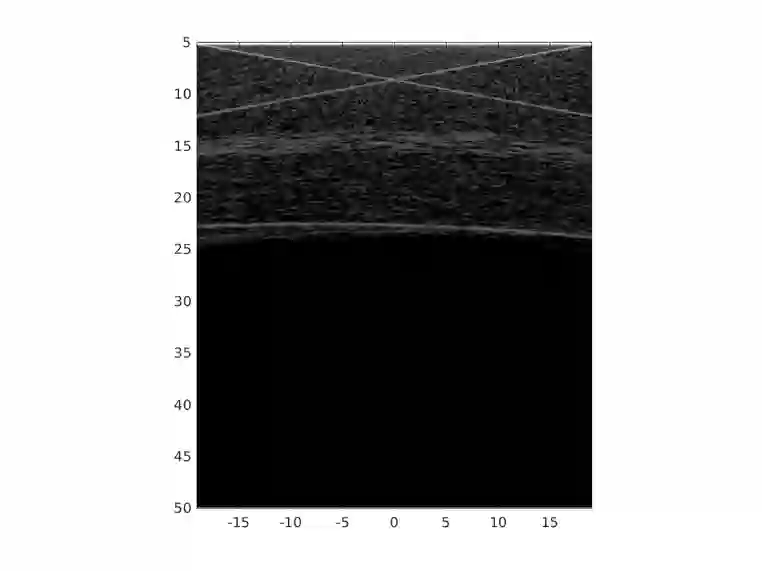

In plane-wave imaging, multiple unfocused ultrasound waves are transmitted into a medium of interest from different angles and an image is formed from the recorded reflections. The number of plane waves used leads to a trade-off between frame-rate and image quality, with single-plane-wave (SPW) imaging being the fastest possible modality with the worst image quality. Recently, deep learning methods have been proposed to improve ultrasound imaging. One approach is to use image-to-image networks that work on the formed image and another is to directly learn a mapping from data to an image. Both approaches utilize purely data-driven models and require deep, expressive network architectures, combined with large numbers of training samples to obtain good results. Here, we propose a data-to-image architecture that incorporates a wave-physics-based image formation algorithm in-between deep convolutional neural networks. To achieve this, we implement the Fourier (FK) migration method as network layers and train the whole network end-to-end. We compare our proposed data-to-image network with an image-to-image network in simulated data experiments, mimicking a medical ultrasound application. Experiments show that it is possible to obtain high-quality SPW images, almost similar to an image formed using 75 plane waves over an angular range of $\pm$16$^\circ$. This illustrates the great potential of combining deep neural networks with physics-based image formation algorithms for SPW imaging.